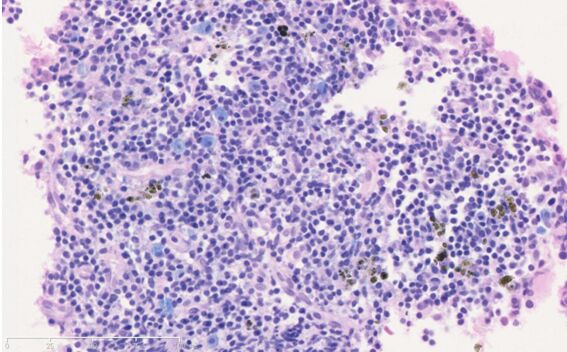

骨髓穿刺组织HE切片120例,其中含三系骨髓细胞超过40%的病例78张进行HE-天青II染色。HE-天青II染色切片中各系骨髓细胞形态完整,核膜核仁清晰,核浆对比清晰,不同发育阶段的红系、粒系、巨核系胞浆嗜碱性差异明显,粒系细胞胞浆的嗜酸性颗粒、嗜碱颗粒清晰,对比明显 (图A、B)。78例HE-天青II染色切片中观察到嗜碱性粒细胞的5例(6.4%)。相同病例对应的HE染色各系骨髓细胞形态完整,核膜核仁清晰,核浆对比清晰,嗜酸性粒细胞胞浆颗粒清晰,但胞浆嗜碱性弱,不同发育阶段的骨髓细胞胞浆嗜碱性差异不明显。78例HE染色切片中观察到嗜碱性粒细胞的0例(0%)。其中一例骨髓HE-天青II染色切片中局部显示有较多嗜碱性粒细胞,在HE染色切片相同区域中未观察到嗜碱性粒细胞的存在,与嗜碱性粒细胞形态特点相似的细胞胞浆颗粒显示具有嗜酸性(图C、D)。

图A:病例一(HE-天青II染色)

图B:病例一(HE染色)

图C:病例二(HE-天青II染色)显示嗜碱性粒细胞

图D:病例二(HE染色)在HE-天青II染色中胞浆嗜碱性颗粒在HE染色中显示为嗜酸性